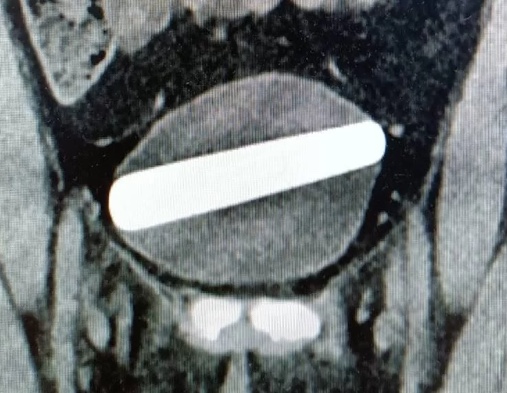

Exames de imagem mostraram que depois de passar pela uretra, o objeto acabou se posicionando na horizontal na bexiga.